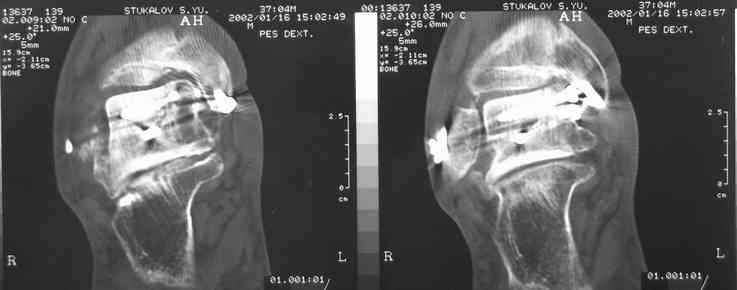

Случай с множественным оскольчатым переломом тарана оперированный из двойного доступа.

Через 2 мес.:

Через 8 мес.:

Через 14 мес.:

На ренгенограмме не уловил многоскольчатость тарана, чтобы доказать, конечно, можно было исследовать на КТ, потом КТ дает ориентацию фрагментов.

Два фрагмента суставной поверхности тарана можно восстановить боковой компрессией шурупами и дополнительно костная пластика.

(кстати, на нашем случае была применена костная пластика-allograft crouton для заполнения дефектов)